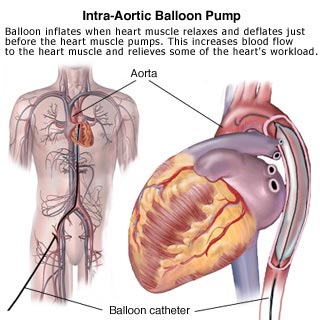

L'aorta è il principale vaso del sistema arterioso dal quale originano le arterie della grande circolazione che trasportano il sangue ossigenato dai polmoni allorganismo. Origina dal ventricolo sinistro del cuore attraverso lorifizio aortico ed è divisa in aorta ascendente, arco aortico ed aorta discendente, della quale si distinguono una parte toracica ed una addominale. Termina a livello della quarta vertebra lombare dove si biforca nelle due arterie iliache. La struttura elastica della tonaca media permette all'aorta di ammortizzare l'onda pressoria che si imprime sul tronco arterioso ad ogni battito cardiaco. L'aneurisma si forma quando le fibre della tonaca media si scompaginano, degenerano o si assottigliano, e i meccanismi riparativi le rimpiazzano con tessuto fibroso che essendo anelastico, tende a sfiancarsi sotto l'impatto pressorio.

L'aorta è il principale vaso del sistema arterioso dal quale originano le arterie della grande circolazione che trasportano il sangue ossigenato dai polmoni allorganismo. Origina dal ventricolo sinistro del cuore attraverso lorifizio aortico ed è divisa in aorta ascendente, arco aortico ed aorta discendente, della quale si distinguono una parte toracica ed una addominale. Termina a livello della quarta vertebra lombare dove si biforca nelle due arterie iliache. La struttura elastica della tonaca media permette all'aorta di ammortizzare l'onda pressoria che si imprime sul tronco arterioso ad ogni battito cardiaco. L'aneurisma si forma quando le fibre della tonaca media si scompaginano, degenerano o si assottigliano, e i meccanismi riparativi le rimpiazzano con tessuto fibroso che essendo anelastico, tende a sfiancarsi sotto l'impatto pressorio.